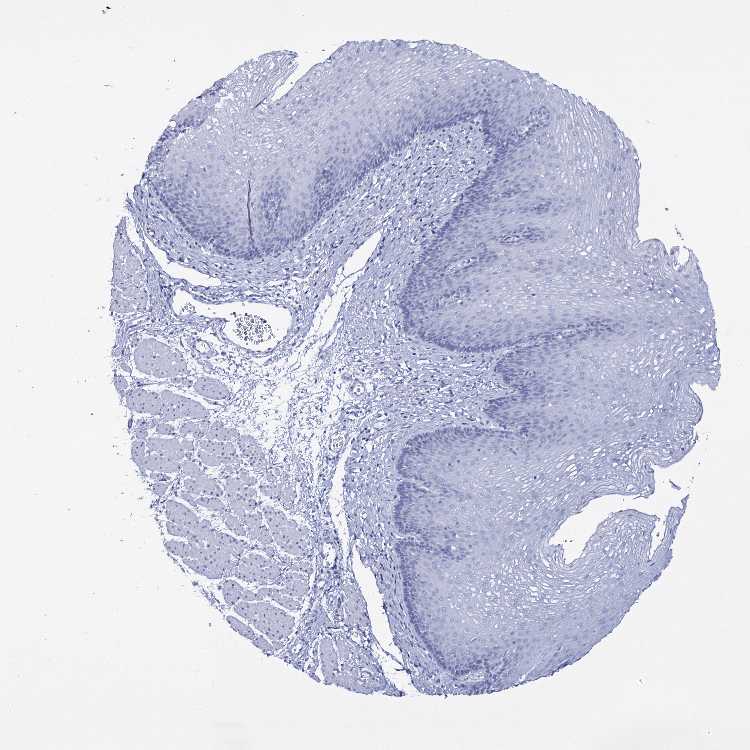

TISSUE PRIMARY DATA ESOPHAGUS Show tissue menu

Esophagus

ESOPHAGUS - Antibody stainingi

Antibody staining in the annotated cell types in the current human tissue is reported as not detected, low, medium, or high, based on conventional immunohistochemistry profiling in selected tissues. This score is based on the combination of the staining intensity and fraction of stained cells.

Each image is clickable and will lead to virtual microscopy that enables deeper exploration of all samples and also displays staining intensity scores, fraction scores and subcellular localization as well as patient and tissue information for each sample.

Antibody HPA039989

Squamous epithelial cells Not detected